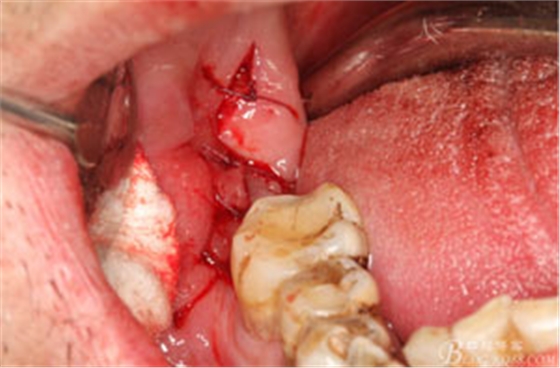

圖12. 先取出48牙冠

圖13.從頰側(cè)和舌側(cè)兩個(gè)方向用挺。挺出牙根

圖14.清理拔牙創(chuàng),并放置膠原蛋白海綿。